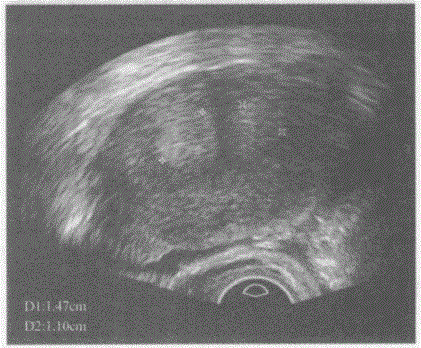

临床资料:女,25岁,自诉月经不规则。超声综合描述:横切面子宫底部平滑,横径增宽,内可见两个子宫内膜回声,中央有条样分隔,内膜汇合于子宫中下部呈"Y...

问题 临床资料:女,25岁,自诉月经不规则。 超声综合描述:横切面子宫底部平滑,横径增宽,内可见两个子宫内膜回声,中央有条样分隔,内膜汇合于子宫中下部呈"Y"形。 超声提示:

选项 A.完全性纵隔子宫 B.不完全性纵隔子宫 C.双子宫 D.双角子宫

答案 B